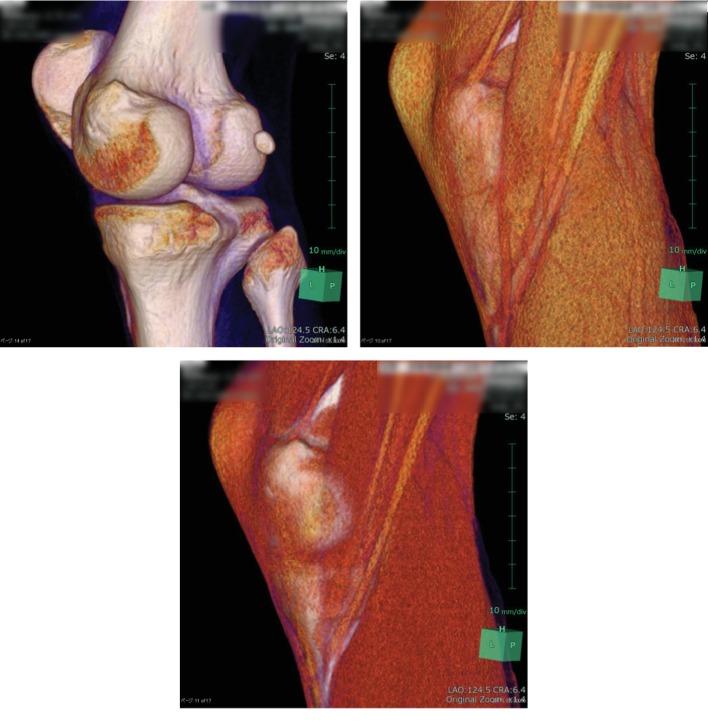

We report the case of painful snapping pes syndrome caused by the gracilis tendon. A 26-year-old man presented with acute right knee pain and restricted extension. Although snapping could not be reproduced due to severe pain, the snapping of the gracilis tendon could be specifically diagnosed using ultrasonography and lidocaine injection. Because of the failure of conservative treatment, surgery was performed. The distal attachment of the gracilis tendon was released, and the symptom disappeared quickly. There was no recurrence at the 10-month follow-up.

摘要

我们报告一例由股薄肌腱引起的疼痛性弹响足综合征病例。一名26岁男性出现右膝急性疼痛和伸展受限。尽管由于剧痛无法重现弹响,但通过超声检查和利多卡因注射可明确诊断为股薄肌腱弹响。由于保守治疗无效,遂行手术。松解了股薄肌腱的远端附着点,症状迅速消失。10个月随访时无复发。